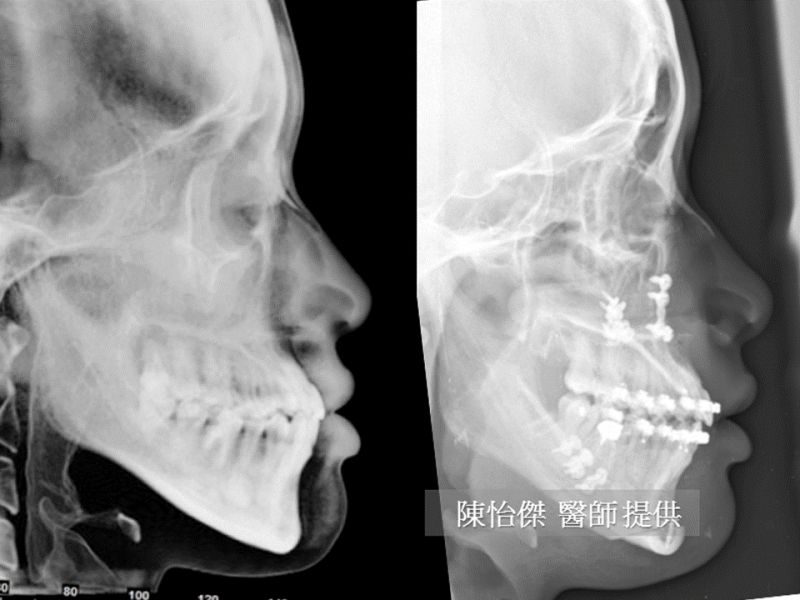

上图左边是治疗之前,从侧面看有轻微戽斗,下巴较突出,但是咬合正常。右图是手术后一周的情况,虽然还在肿胀的阶段,但是仍然可以看出脸型的变化,以及上下唇变得比较自然饱满的感觉。

如果从鼻尖到下巴最前端画一条直线当作参考线,就可以更清楚地看到上下唇相对位置的改变。虽然只差了一点点,但是在外观上却可以带来明显的改变。